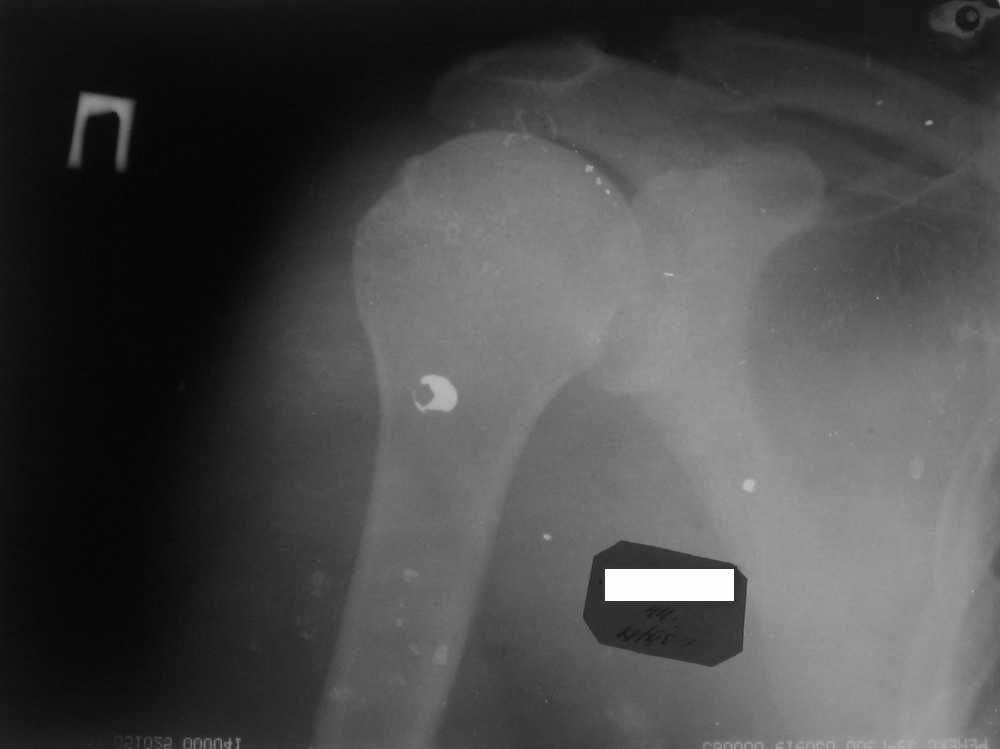

Мужчина, 45 лет. Профессионально занимается культуризмом. При жиме лёжа

возникают резкие боли в левом ключично-акромиальном сочленении в течение

3 лет. В покое болей нет.

Имя     : IMG_3098.jpg